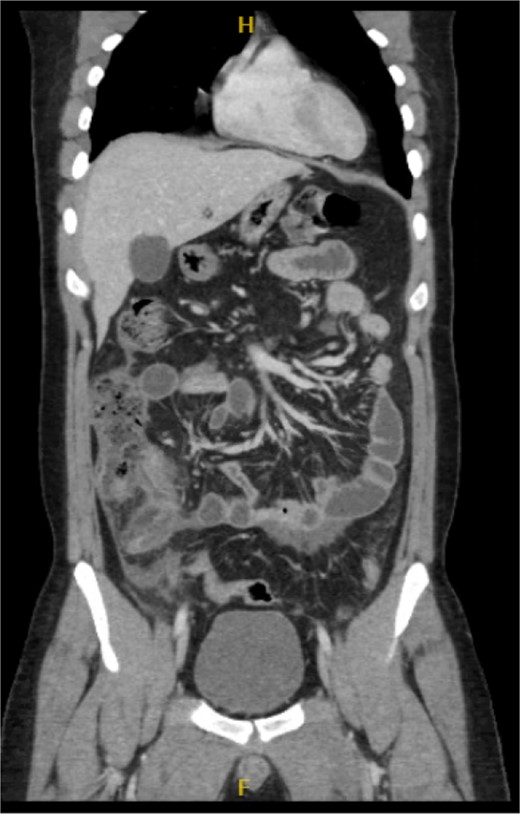

His laboratory tests revealed a white blood cell (WBC) count of 7.8 × 103; all other blood workups were within normal ranges. An abdominal CT scan showed a dilated fluid field in the appendix measuring ~1.8 cm in diameter, with fat stranding, with few areas of decreased well enhancement, and a possible defect in the distal portion of the appendix with phlegm formation (Figs 1–3). All other organs, including the spleen, were unremarkable for any positive findings, with no evidence of free fluid or any splenic injury at the time of the CT scan. The patient was admitted under general surgical care, started on intravenous antibiotics, and was scheduled for laparoscopic exploration and appendectomy. Intraoperative findings included an inflamed appendix and perforation at the midpoint. The patient had an uneventful recovery. The patient was discharged in good condition on postoperative Day 2, with follow-up in the outpatient clinic.

Radiological findings in CT images revealed signs of appendicitis: an enlarged appendicular diameter >6 mm, an appendicular wall thickness >2 mm, mesenteric fat stranding, the presence of an appendicolith, and signs of complications, including perforation or the formation of a peri-appendiceal abscess [10–12]. Careful assessment requires careful medical history taking, physical examination, and radiological investigations with ultrasound or CT scans, which are more sensitive and specific. A high index of suspicion of post-traumatic appendicitis is required because of the rarity of the condition. Treatment includes intravenous antibiotic administration and appendectomy.